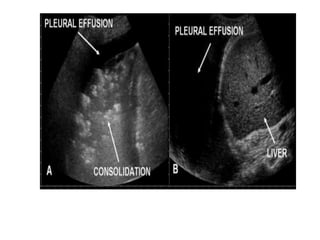

Pleural

effusion

Lower lobe

Tissue pattern representativeof Alveolar Consolidation Presence of hyperechoic punctiform imagesrepresentative of air bronchograms Pleural effusion Lower lobe